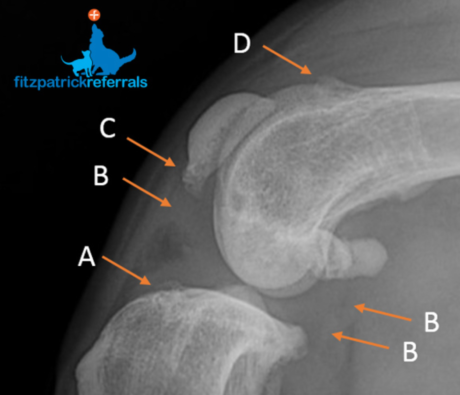

The classical radiographic presentation in patients with MPL and CCL are demonstrated in the radiographs in this article. A full pelvic limb radiographic evaluation, including ventro-dorsal extended hips and orthogonal views of the stifles, is recommended before making any surgical decisions. The complexity of MPL and concurrent CCL disease means treatment must be tailored to the individual taking into account patient size, skeletal conformation and grade of patellar luxation.